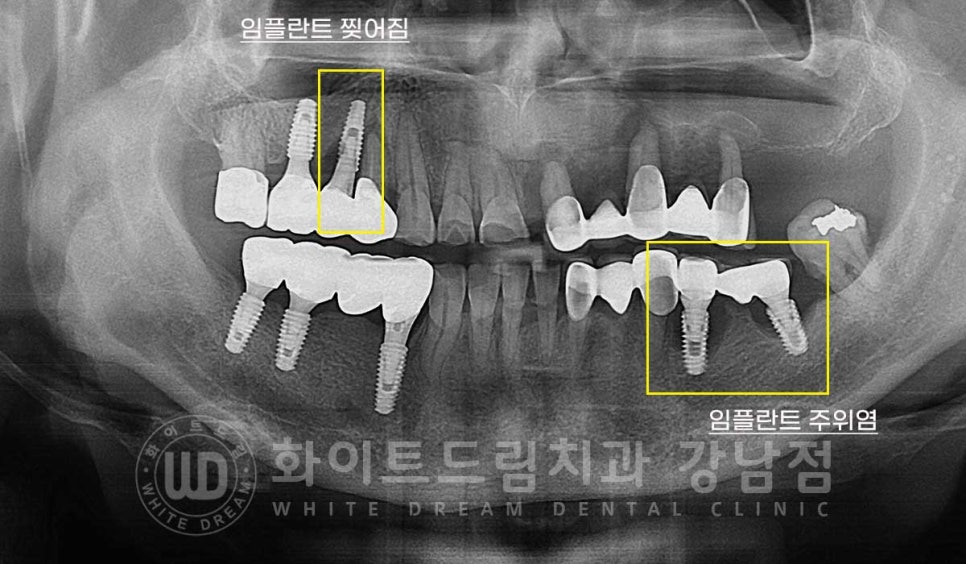

임플란트 재수술의 주원인 / 찢어짐 & 주위염

10번대 어금니 부위는 임플란트가 찢어지면서 주위 염증이 생겨있고

40번대 어금니는 임플란트 주위염으로

증상은 모두 '임플란트 흔들림'이 발생하고 있는데요.

▲ 증상이 더 시급한 20번대 브릿지, 30번대 임플란트 어금니 부위

그럼 치료를 진행한 부위, 20, 30번대 상태는 어땠을까요?